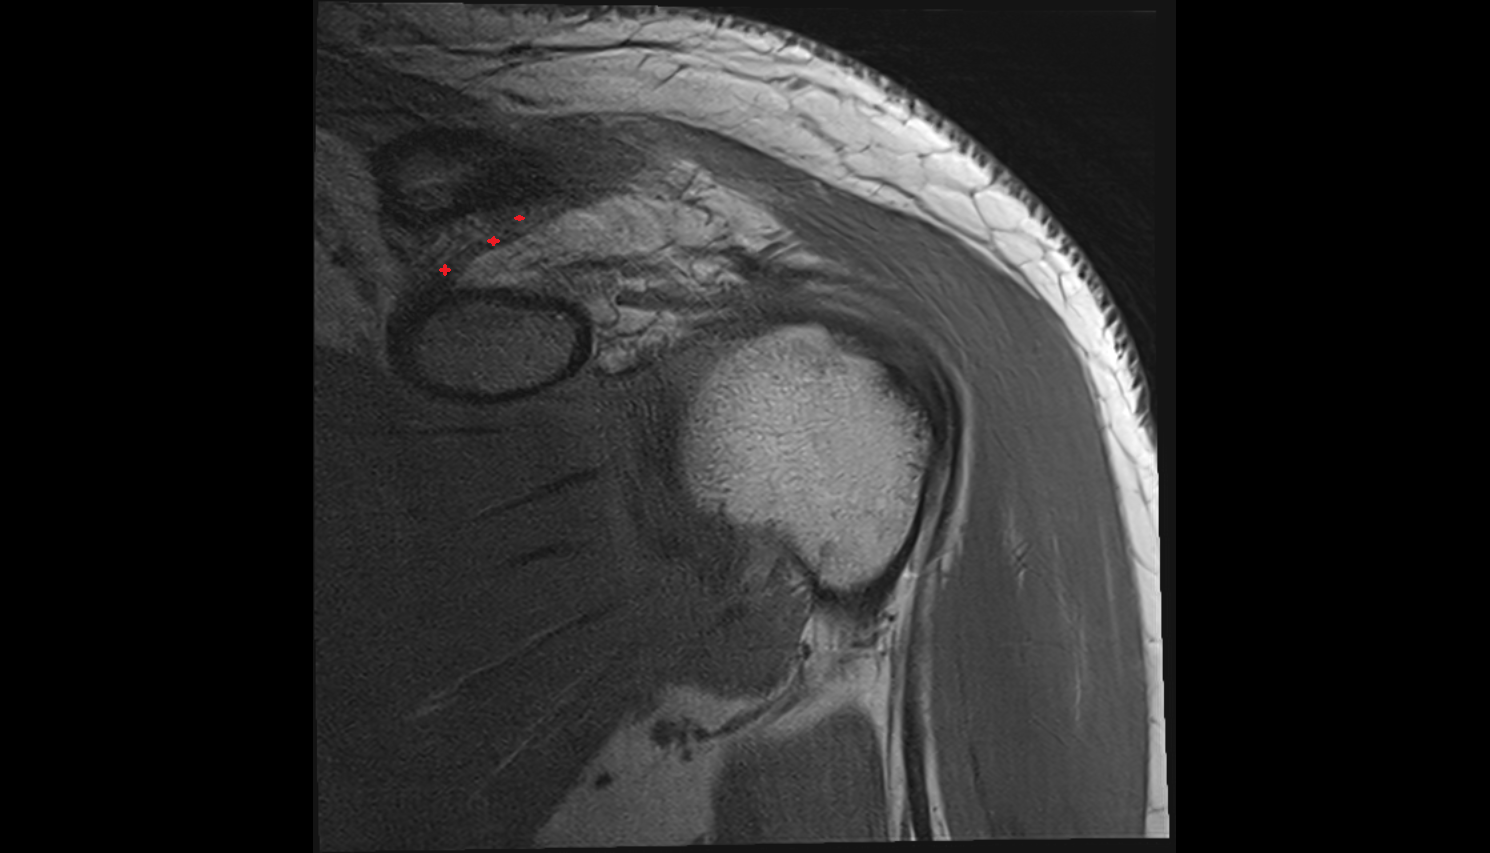

- Supraspinatus tendon

- Shoulder joint (glenohumeral joint)

- Subacromial space